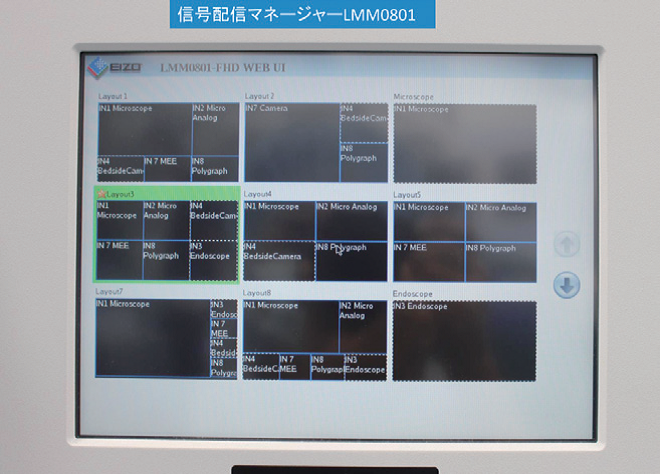

信号配信マネージャLMM(Large Monitor Manager)はCuratORの中心にあり、各種映像の集約・切り換えや、キーボード・マウスを共有するKVM機能、マウスやタッチパネルによる直感的なレイアウト切り換えを実現する。

これら機器を集中操作するソフトウェアは、必ずしもIT機器に詳しいとは限らない医療スタッフが直感的に全ての機器を操作できるよう設計されている(図2)。

手術用大型モニタの特徴は、基本的には画像の高精度化・大型化である。情報信号配信マネージャーは、マルチレイアウトで手術中に手技に応じて必要となる各種画像を自由なフレームサイズで術者に提示できる(図2)。さらに、大型モニタを介して各種の情報をスタッフが共有できる。